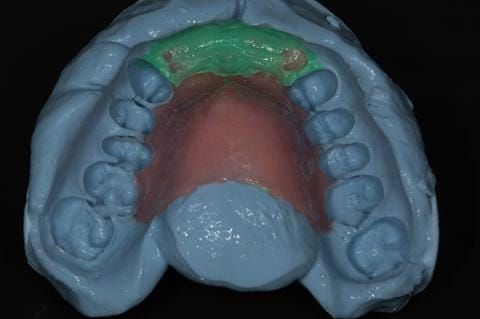

- Extract the upper 2-2 teeth and replace with an interim acrylic based partial denture. Reline the interim denture over 9 - 12 months, replacing with a definitive cobalt chromium based partial denture. The definitive denture would ideally be designed as an occlusal protective splint to reduce the the potential for mechanical wear and breakages of the moderately/heavily restored maxillary dentition. In addition, should further upper teeth require extraction they could be added on to the denture cobalt chromium framework - therefore a new prosthesis would not be required as future teeth are lost. This option would produce an excellent aesthetic outcome. This is the option the patient chose to have.

Following consultation and second discussion appointment the patient chose to have option 3 namely, a maxillary cobalt chromium based partial denture/protective occlusal splint. The clinical situation and treatment process is shown in detail below with photographs. The patient was successfully rehabilitated with this and her quality of life considerably improved. The clinical work was provided by Finlay and the technical work by Rowan.